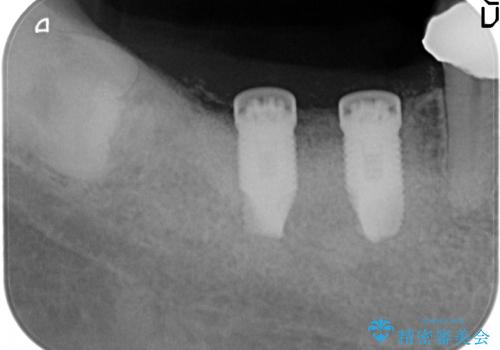

- 失った右下奥歯の機能回復を求めて来院されました。

取り外しの必要な入れ歯、もしくは手術の必要なインプラントのご提案を行い、しっかりと奥歯で物を噛みたいとの要望からインプラント治療を計画します。

インプラントの埋入には十分な骨量が必要ですが、虫食い状に骨が足りなかった為インプラントの埋入と同時に骨の増成を行いました。